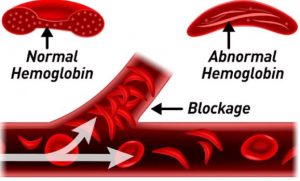

Beim gesunden Blut (links) sind die Blutzellen wie

Billardkugeln und der Sauerstofftransport ist 100%,

Blutzellen der GENgeimpften sind zerknittert,

verhaken sich, provozieren Blutgerinnsel+Thrombosen.

UND: Sauerstofftransport ist kaum noch möglich,

Dauermüdigkeit, weil alle Organe unterversorgt sind.

With healthy blood (left) the blood cells are like

billard balls and there is full 100% oxygen

transport, so the person is sportive and fit. The

blood cells of GENE vaccinated are crumpled, they

stick together forming clots and thromboses. AND:

oxygen transport is hardly possibble, eternal

tiredness comes up because all organs suffer lack of

oxygen.

roten Blutkörperchen so verändern, dass sie

zusammenkleben. Das erklärt die

Ein Hauptgrund für Myokarditis, Schlaganfälle und

Herzinfarkte sind verstopfte Blutgefäße,

einschließlich Arterien, Venen und Kapillaren, von

denen jede eine spezifische Rolle im Prozess der

Zirkulation von Sauerstoff und Nährstoffen spielt.

Effekt? Der Moderna-mRNA-Covid-Impfstoff verändert die

Form und Klebrigkeit der roten Blutkörperchen, wodurch

sie gerinnt. Das erste Diagramm unten zeigt gesunde

Blutkörperchen und nach der Covid-Impfung haben Sie

mutierte, deformierte rote Blutkörperchen,

aufgestockte Proteine und den Klebrigkeitsfaktor, der

tödliche Blockaden verursacht. Es ist wie eine

Also ich kann dazu noch folgendes sagen: Das Blutbild

praktisch aller Geimpften weist ein Verklumpen der roten

Blutkörperchen aus. Damit sinkt die Oberfläche dieser! Die

Folge ist nur logisch = verminderte Sauerstoff Versorgung

Blut verklumpt

transportiert keinen Sauerstoff mehr 20.9.2021

Ich kann es nur erneut wiederholen: Wie zu Teufel sollen

verklumpte rote Blutkörperchen, die wie eine Münzen Rolle

aussehen, für die Sauerstoff Versorgung noch Gewähr

übernehmen? Und dazu, da sie durch die Verklebung nicht

mehr verformbar sind durch die Kapillar Gefäße hindurch

kommen???